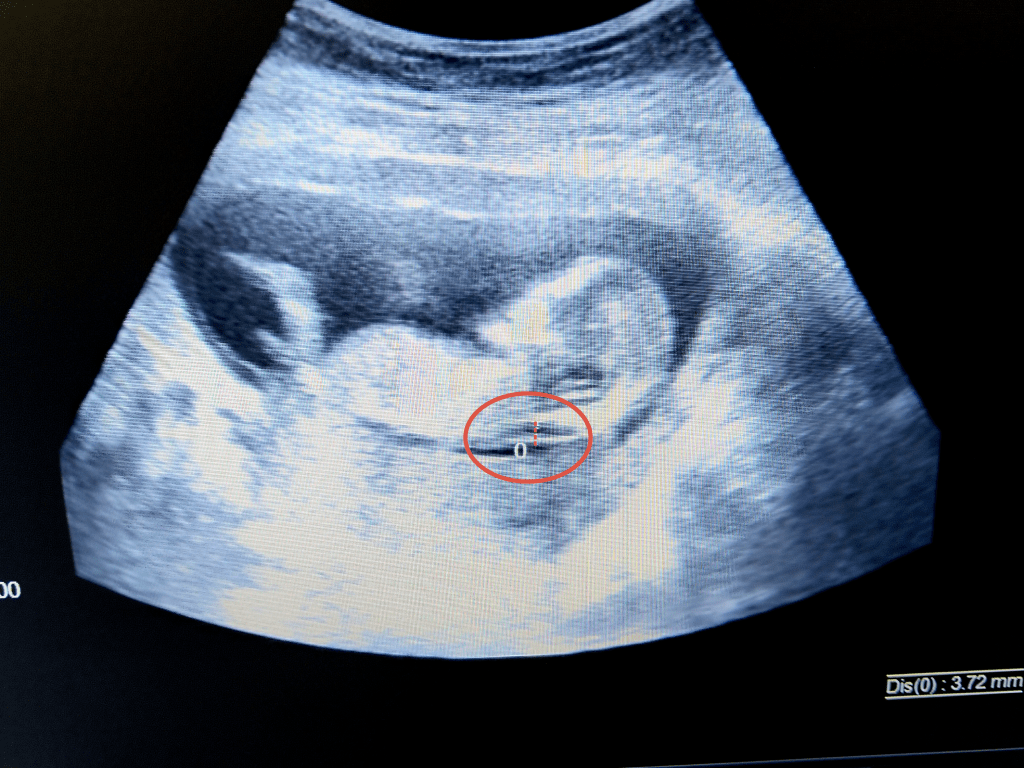

Nakkefolden er en væskespalte, som findes under huden ved nakken. Væskeophobningen kan kun registreres omkring slutningen af 1. trimester, mellem 11 og 14 ugers graviditet, når fosteret måler et sted mellem 4,5 og 8,4 cm. Jo tykkere nakkefolden er, jo større er sandsynligheden for Downs syndrom eller andre kromosomtilstande.

Hvor tyk må nakkefolden være?

Måling af nakkefold skal gerne være mindre end eller lig med 3 mm., men en tyk nakkefold vil ikke i sig selv betyde, at et barn fødes med en kromosomafvigelse. Nakkefoldens tykkelse står nemlig ikke alene, når den såkaldte risikovurdering laves, da din alder og svaret på blodprøven (doubletesten) altid medregnes i ligningen.

Udover at se på nakkefoldens tykkelse vil en nakkefoldsskanning vise barnets længde fra hoved til numse, den såkaldte crown rump length (CRL). Dette mål vil indimellem skubbe til en tidligere fastsat terminsdato, fordi der ved ultralyd før 20. uge menes, at alle fostre har samme størrelse i de forskellige graviditetsuger.